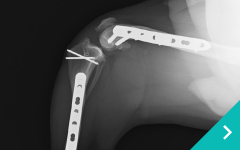

関節鏡を用いた関節内精査と低侵襲手術、関節外法やTPLO法による膝関節再建、MPLG4に対する矯正骨切りを用いた整復、LCPを用いた骨折整復など難易度の高い手術にも対応しております。

前十字靭帯断裂(TPLO)

前十字靭帯断裂

(TPLO)